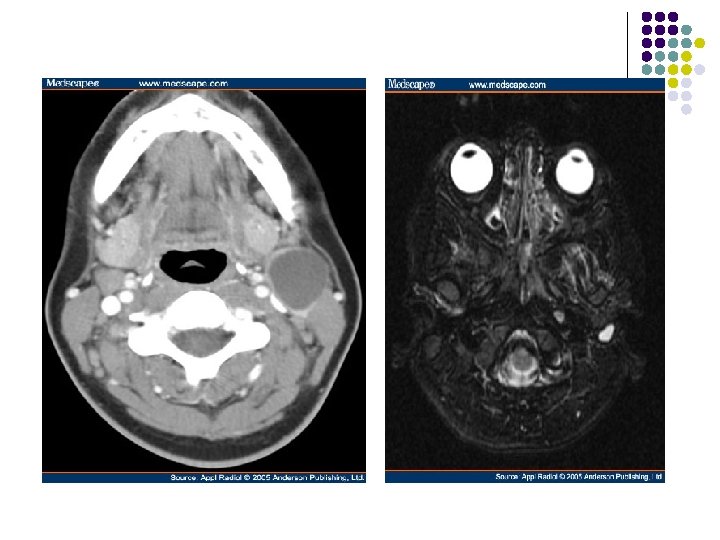

l First branchial cleft cyst. I. Contrast-enhanced axial CT at the level of the hyoid bone reveals an ill-defined, nonenhancing, water attenuation mass posterior to the right submandibular gland. l Second branchial cleft cyst. Contrast-enhanced axial CT at the level of the hyoid bone reveals a large, well-defined, nonenhancing, water attenuation mass on the anterior border of the left sternocleidomastoid muscle.

l Ultrasound of an uncomplicated branchial cyst. Note the absence of septations and the through enhancement. Axial contrast enhanced CT showing a right sided low attenuation branchial cyst.

Axial T 1 -weighted image shows a well-defined mass (m) along the anterior border of the left sternocleidomastoid muscle (arrowhead), lateral to the carotid space (white arrow), posterior to the submandibular gland (black arrow)—the classic location for a second branchial cleft cyst. The cyst typically displaces the sternocleidomastoid muscle posteriorly or posterolaterally, pushes the vessels of the carotid space medially or posteromedially, and displaces the submandibular gland anteriorly. Increased signal intensity of the mass is due to either proteinaceous debris or prior hemorrhage. (b) Axial T 2 -weighted image reveals moderate to marked hypointensity of the mass (m), consistent with accumulation of proteinaceous debris or hemorrhage.

l Contrast-enhanced axial CT at the level of the hyoid bone reveals an ill-defined, nonenhancing, water attenuation mass (m) posterior to the right submandibular gland (g).

Contrast-enhanced axial CT at the level of the thyroid cartilage reveals a large, well-defined, nonenhancing, water attenuation mass (m) deep to the right sternocleidomastoid muscle (s), medially displacing the common carotid artery and internal jugular vein.